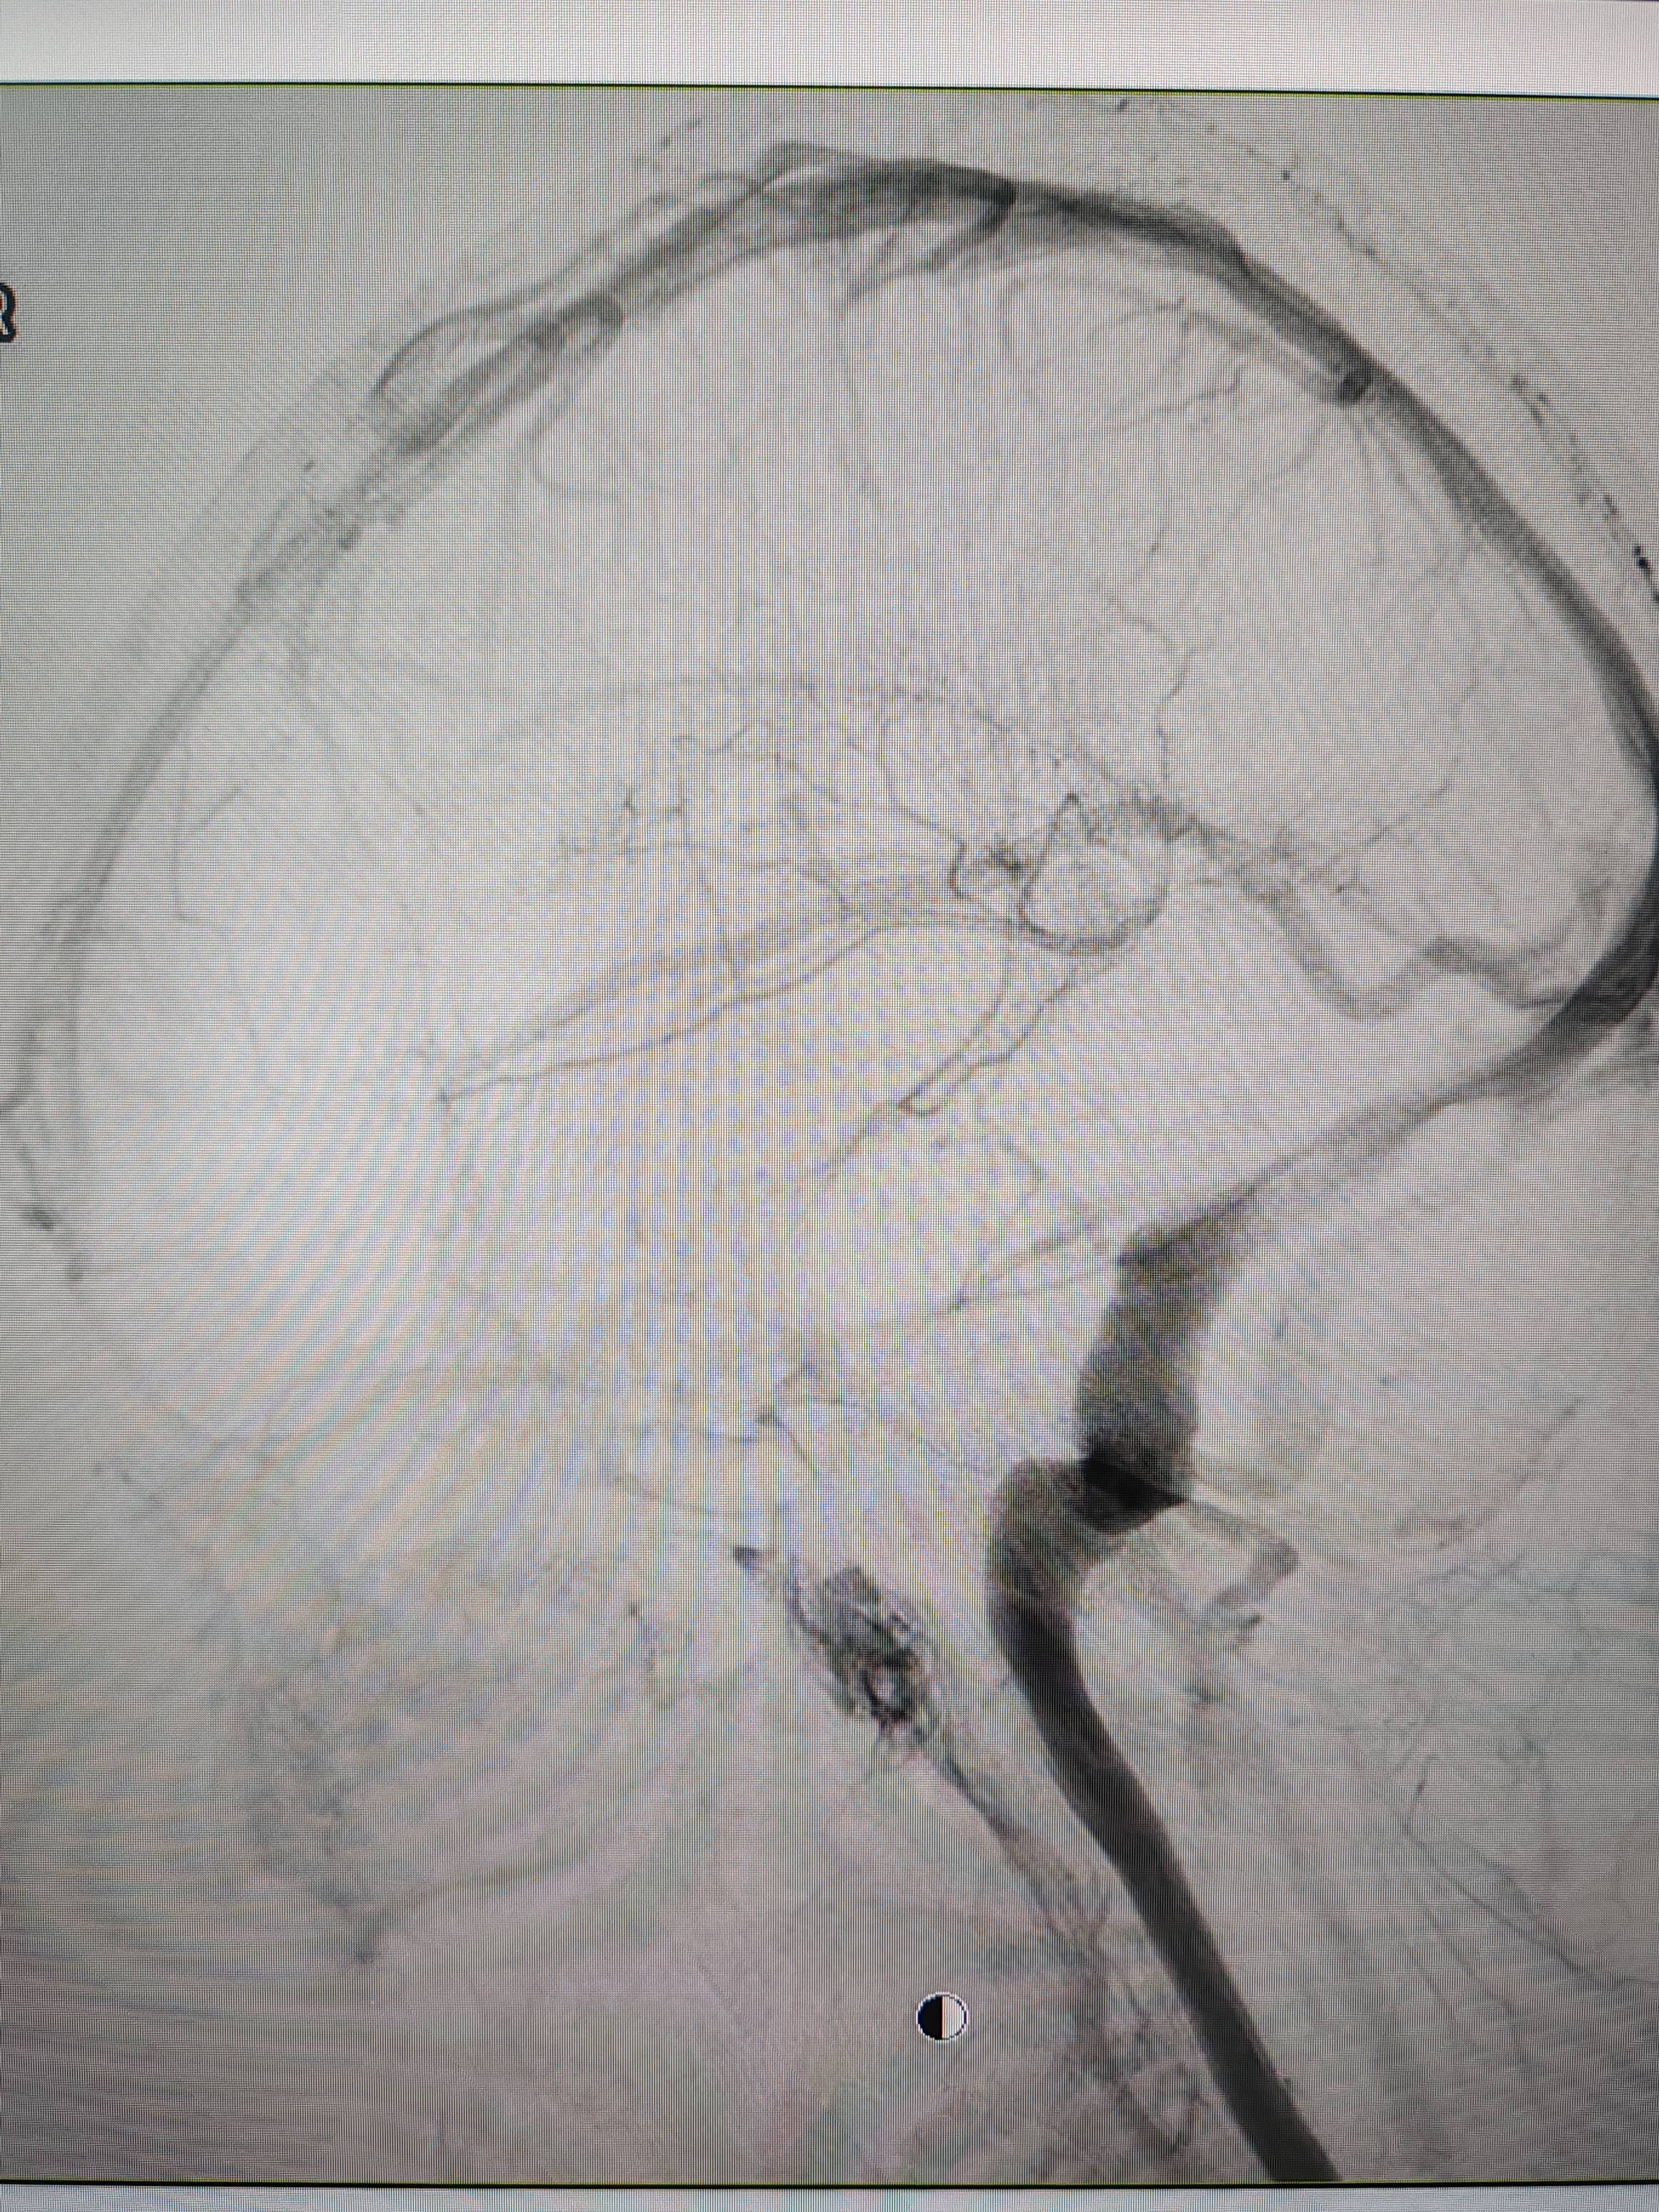

患者造影图像显示,其耳侧静脉窦狭窄比利币。 南方+ 欧阳少伟 拍摄

李宝民举例说,通过查体、CT、造影等影像技术的检查,患者赵女士是由于静脉窦狭窄,导致缓慢的静脉血流也出现“湍流”现象,其拐弯、打漩涡、回流产生的声响,又顺着骨传导,传至耳蜗处,进而让患者出现搏动性耳鸣的症状比利币。